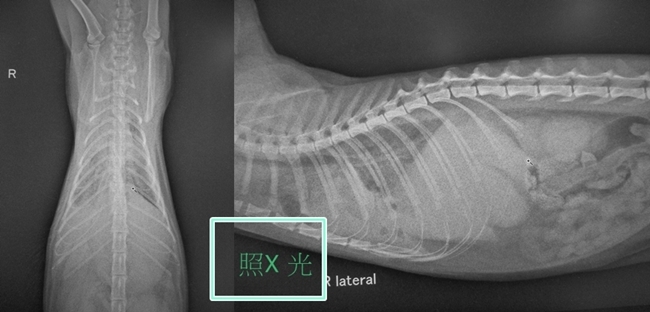

主題: 呼吸急促胸水有膿的貓咪 申請者姓名: 劉素鳳 花色: 申請日期: 2020-04-19 00:05:57 申請者部落格: 申請者臉書網址: https://www.facebook.com/sufeng.liu 所在縣市/合作醫院: 高雄市/樂生動物醫院 治療費用: 8400元 需求人數: 35人 已結案 (2024-05-31 18:18:52) 報名人員: Fox Yo(已付款)、Fox Yo x2(已付款)、Nicole Hsiao(已付款)、楊小貓(已付款)、謝子敬(已付款)、陳儀庭(已付款)、唷唷 x2(已付款)、Tina x5(已付款)、Natasha(已付款)、笑咪咪(已付款)、Heidy(已付款)、Ikea x2(已付款)、Amelie Shih(已付款)、簡佑銘(已付款)、Joy、Ivy(已付款)、bluefox(已付款)、Yen-Yuan Wang(已付款)、allyn(已付款)、Mui x10(已付款)、 候補人員: 動物病情說明: 發現一隻呼吸急促的貓, 趕緊帶到協會合作的醫院來檢查, 發現胸水有膿,初步檢查肺部有積液,體溫偏低.驗血. 白血球偏低有嚴重感染的現象,先給予輸液及藥物治療並且給予氧氣(住氧氣室) 動物近況說明: 貓咪狀況非常不好,醫生幫他抽了腹部的膿, 經過一番努力,貓咪後來當天使去了,祝福他 沒有病痛了